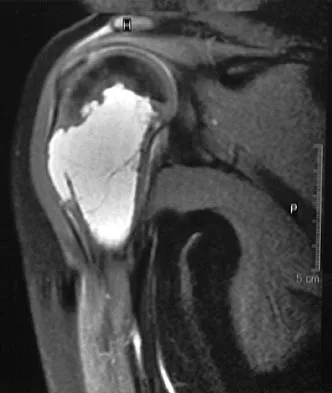

A 32-year-old woman with systemic lupus erythematosus treated with methotrexate and oral corticosteroids reports right groin pain with ambulation and night pain. Examination reveals pain with internal and external rotation and flexion that is limited to 105 degrees because of discomfort. Laboratory studies show a serum WBC of 9.0/mm3 and an erythrocyte sedimentation rate of 35 mm/h. Figures 5a and 5b show AP and lateral radiographs of the right hip. Further evaluation should include

The radiographs show Ficat and Arlet stage 2 osteonecrosis. The femoral head remains round, and there are sclerotic changes in the superolateral quadrant. Patients with systemic lupus erythematosus are at risk for osteonecrosis because of prednisone use and the underlying metabolic changes associated with the condition (hypofibrinolysis and thrombophilia). MRI is the best diagnostic method for detecting osteonecrosis, with a greater than 98% sensitivity and specificity. For this patient, an MRI can assess the contralateral hip for any involvement and can quantify the extent of the lesion. Mont MA, Jones LC, Sotereanos DG, Amstutz HC, Hungerford DS: Understanding and treating osteonecrosis of the femoral head. Instr Course Lect 2000;49:169-185.

- Koval KJ (ed): Orthopaedic Knowledge Update 7. Rosemont , IL, American Academy of Orthopaedic Surgeons, 2002, pp 417-451.